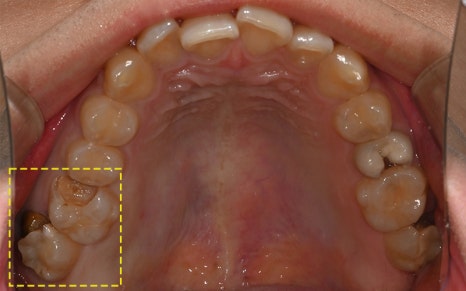

The photos above show the implant that was actually removed.

The screw body had snapped due to metal fatigue,

and around the head there was a large amount of tartar and inflammation.

The surrounding gum bone had melted away,

which eventually led to extraction of the adjacent tooth as well.

In the end, the implant had to be placed again,

and overall reconstruction was needed.